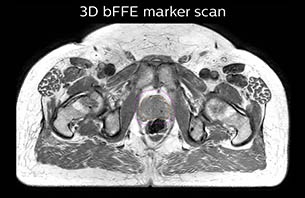

Using the mDIXON and 3D bFFE images, the RT planner marks the position of the nickel-titanium fiducial markers, and contours are transferred to the digitally reconstructed radiographs (DRRs). Reference image matching is based on these markers. “In the rare cases, where visualization of the fiducial markers fails, we do a CT to confirm their location,” Dr. Keyriläinen notes.

MR-only simulation workflow The 3D T1W FFE mDIXON sequence provides in-phase, water and fat images in one acquisition. Target and organs-at-risk are delineated on the 3D T2W TSE images. Prostate GTV is shown in orange, PTV in purple. The 3D bFFE sequence is used by the planner to mark the position of the fiducial markers (gold anchors) and contours are transferred to the digitally reconstructed radiographs (DRRs).